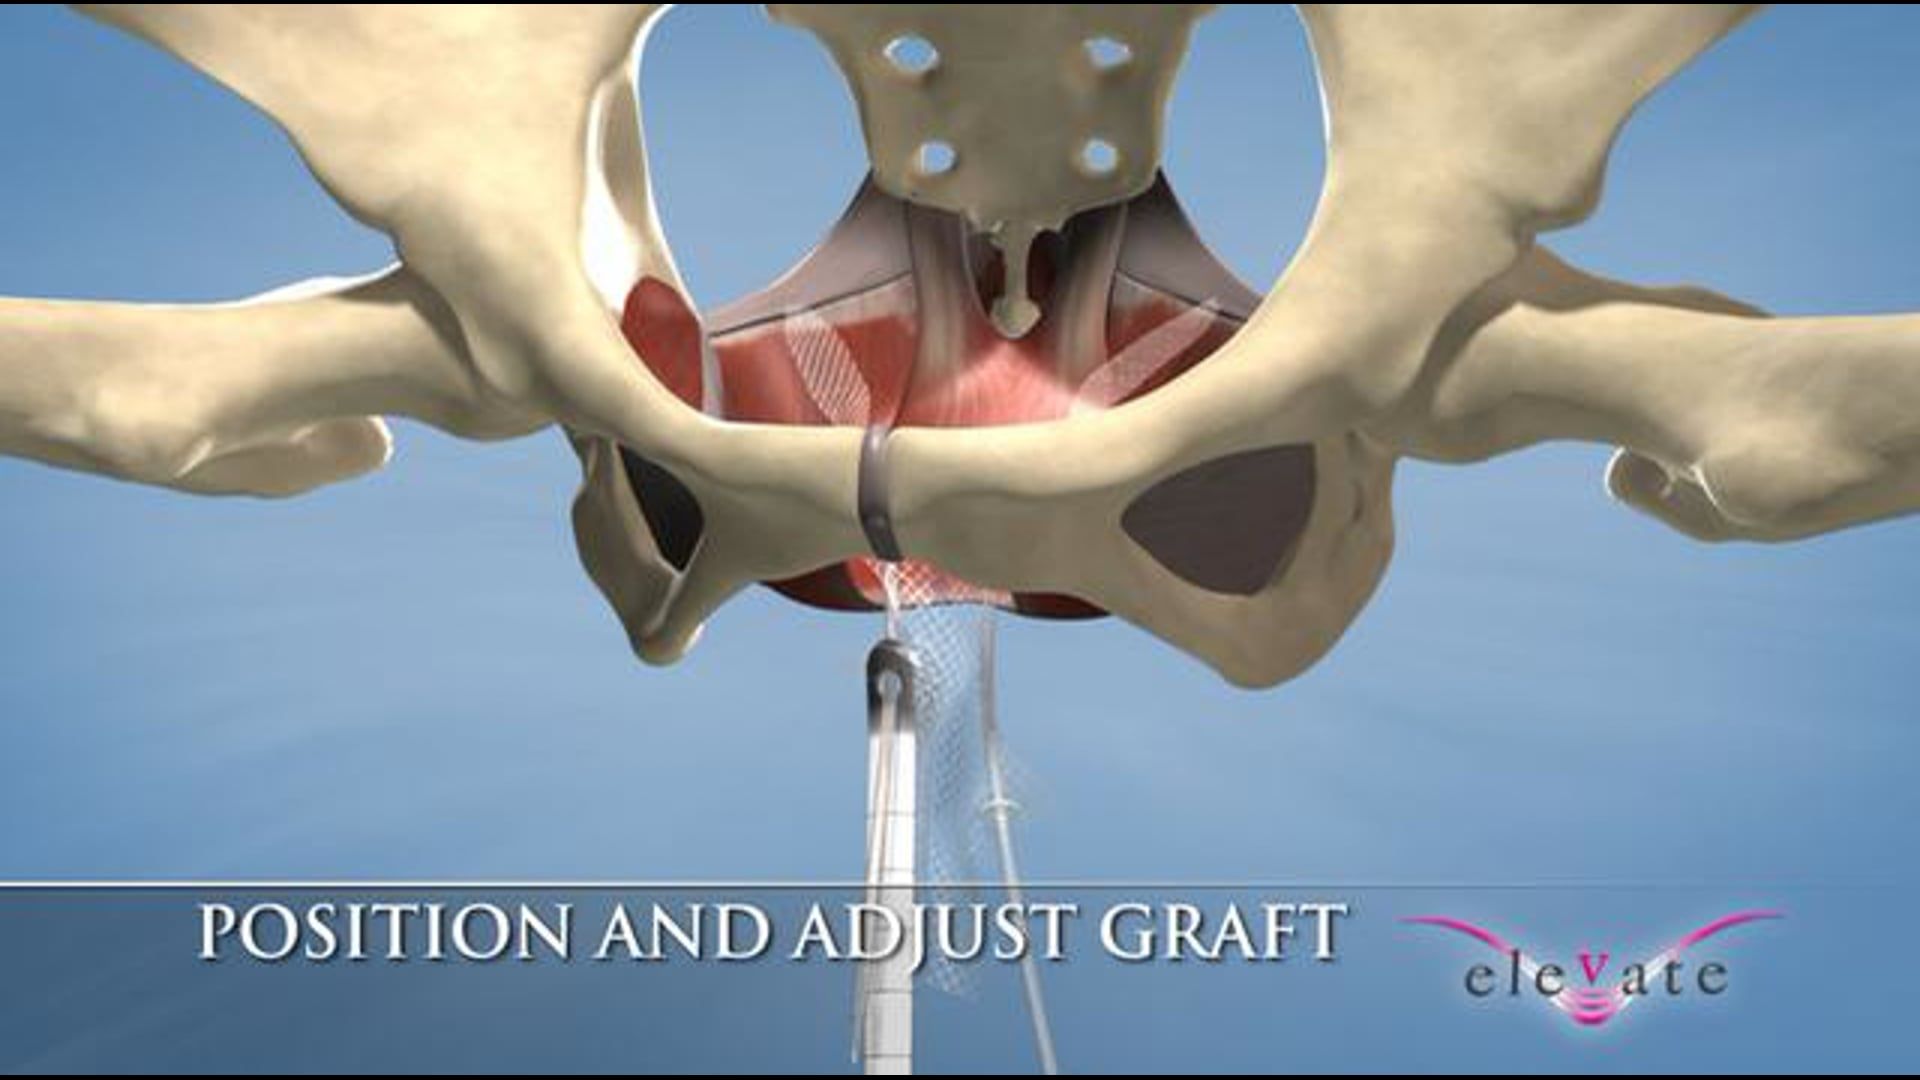

AMS partnered with Ghost Productions, a medical animation and graphics company, to create a series of animations and medical graphics that effectively communicated the benefits of their products. Ghost Productions worked closely with AMS's team to understand the mechanism of action of each product and create a visual representation of the process.

the animations and medical graphics produced by Ghost Productions proved to be instrumental in helping AMS effectively communicate the benefits of their products to their target audience. The visual aids helped potential customers and physicians understand the mechanism of action of each product and the benefits of using them to treat urological and gynecological conditions.